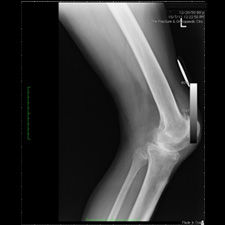

Bilateral Total Knee Replacement was recommended, and performed on July 27th 2011. Since surgery, the patient has made good progress and can now mobilize with the aid of a walker.

His x-rays and clinical examination suggest good early outcome with a fully mobilized patient with pain free knees and the ability to walk independently.

At the present time, he remains under our care and with physiotherapy and self-exercise, he will continue to improve.